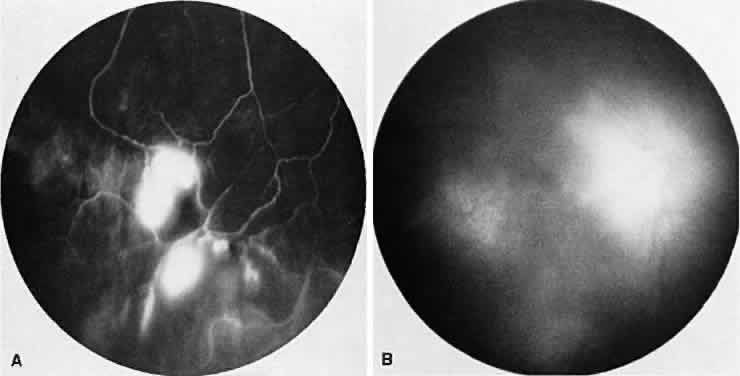

Sympathetic ophthalmia is a rare, bilateral granulomatous, paninflammatory disease that can occur several weeks to years after an ocular injury. Sympathetic ophthalmia is hypothesized to be an autoimmune reaction against a normally sequestered antigen unmasked by an injury. Retinal findings in sympathetic ophthalmia are perivasculitis, papillitis, and yellowish subretinal nodules known as Dalen-Fuchs nodules. Dalen-Fuchs nodules are believed to be transformed retinal pigment epithelium cells or T lymphocytes or both. Areas of choroiditis or granuloma simulating AMPPPE may be seen. Pigmentary disturbance may be noted in the chronic phase of the disease (Fig. 4A and B). Choroidal neovascularization also may develop (see Fig. 4C).

Fig. 4. Sympathetic ophthalmia. A. Areas of pigmentation and small areas of focal atrophy. B. Fluorescein angiogram showing blocked fluorescein corresponding to the areas of pigmentary disturbance with areas of hyperfluorescence representing old areas of inflammation. C. Blocked fluorescence due to subretinal blood in the juxtafovea with associated choroidal neovascularization.

One of two possible fluorescein angiographic findings may be evident. The more common one is identical to Vogt-Koyanagi-Harada syndrome, with early multiple pinpoint retinal pigment epithelial leaks that enlarge with time.11 The second, less common, manifestation is early choroidal hypofluorescence of the Dalen-Fuchs nodules followed by hyperfluorescence in the later phase.12 When exudative retinal detachment occurs, there are confluent areas of subretinal fluorescein pooling.

Two patterns have been identified on ICG angiography.13 The first pattern, observed in a patient with chronic disease, showed hypofluorescent spots in both the intermediate and late phases of the angiogram. The second pattern, reported in a patient with recent onset of the disease, showed hypofluorescent spots in the intermediate phase but faded in the late phase of the angiogram.